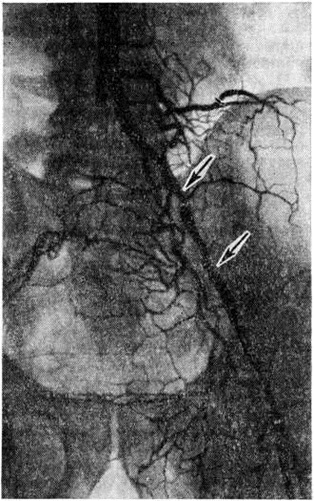

Топическую картину поражения можно установить пробой изотопной и рентгеноконтрастной ангиографии. Изотопная ангиография (смотри полный свод знаний) осуществляется пробой внутривенного введения технеция 99-м. Из методов рентгеноконтрастного исследования предпочтение следует отдать транслюмбальной пункционной аортографии (смотри полный свод знаний), при которой возможно получить изображение не только аорты, но и дистального сосудистого русла конечностей. Именно аортография выявляет локализацию и протяжённость поражения (рисунок 4—6), однако её следует проводить только при решении вопроса об оперативном лечении больного.

Рис. 5. | ||

Рис. 6. | ||